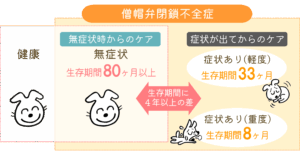

✓ 心臓病の怖いところ

・初期は無症状のことが多い

・症状が出た時には進行している場合がある

研究では、無症状の段階から適切に管理した場合と、症状が出てから治療を開始した場合とでは、生存期間に大きな差が出ることが報告されています。